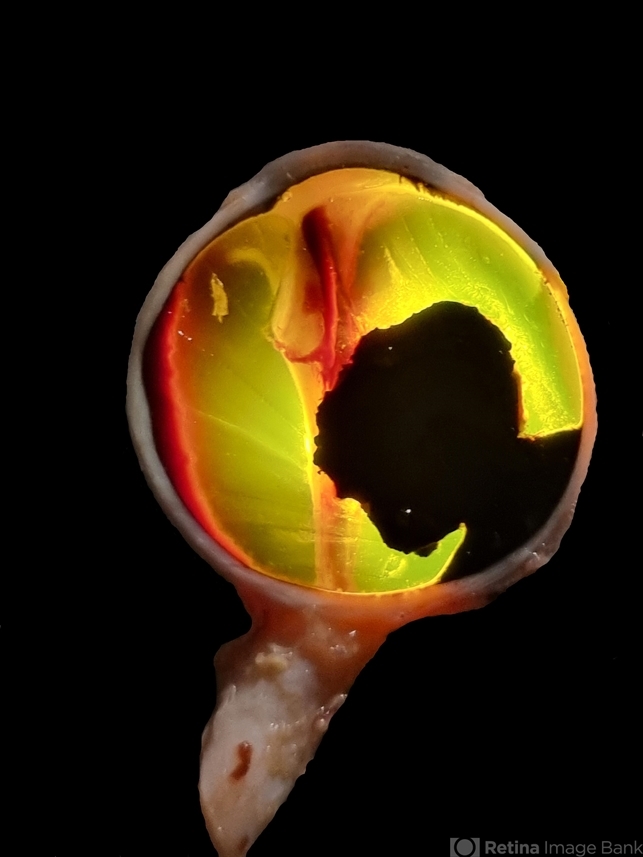

- melanoma, enucleation

- Transillumination of Enucleation specimen of Choroidal Melanoma: anterior chamber is closed. Total secondary retinal detachment with subretinal serous fluid and some subretinal hemorrhages are present.